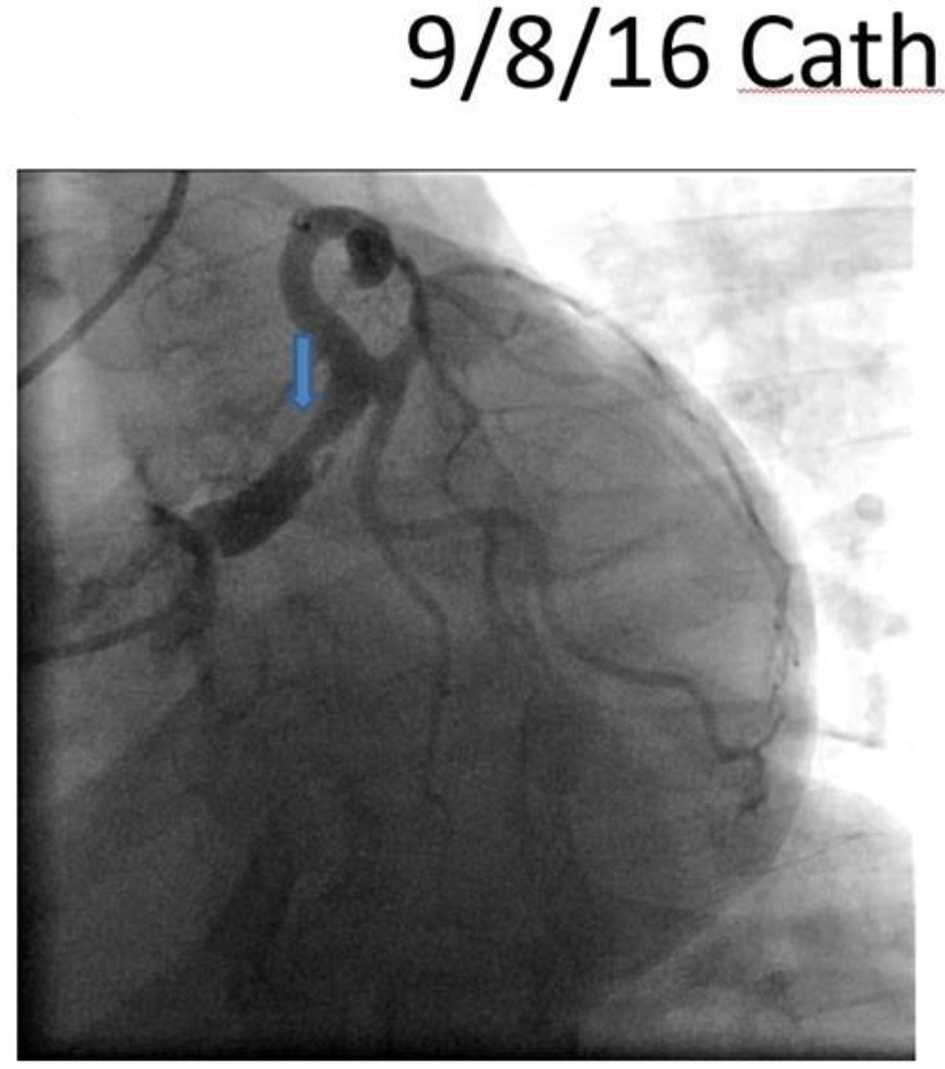

The patient was discharged home with a LifeVest wearable defibrillator on guideline directed medical therapy and was asymptomatic with no events at 3-month follow-up. A repeated angiography revealed continuous angiographic improvement of her left main artery lesion site (Fig. 4), while the IVUS revealed complete resolution of the intramural hematoma (Fig. 5).

![]() Click for large image | Figure 4. Repeat cardiac catheterization showing improved left main lesion (blue arrow). |